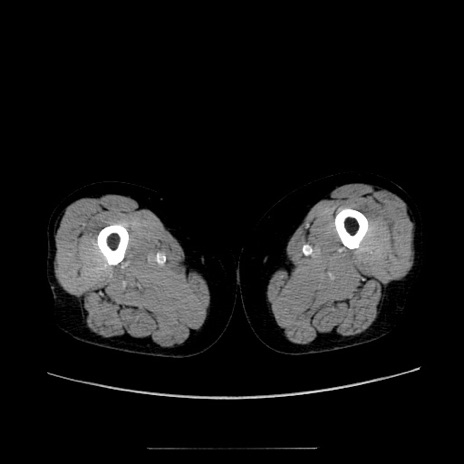

症例5(横断像)

【症例】70歳代女性

【主訴】お腹が張る

【現病歴】1週間くらい前から腹部膨満の自覚あり。昨日夜から増悪したため、本日救急外来受診。

【身体所見】意識清明、BT 36.5℃、BP 165/106mmHg、HR 80bpm、SpO2 98%、腹部:膨満、軟、自発痛・圧痛なし、触診にて不快感あり、腸蠕動音:減弱

【データ】WBC 12600、CRP 1.04